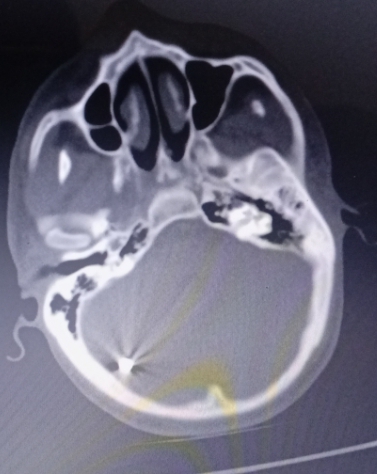

“Beyninde metal parçalar tespit edildi”

Adıyaman Eğitim ve Araştırma Hastanesi’nde yapılan tetkiklerde Ahmed Elhasan’ın beyninde ve kafatasında metalik yabancı cisimler tespit edildi.

Hastane raporlarına göre, hastada bombadan kaynaklı konvülziyon, hemipleji ve quadriparezi (kısmi felç ve kas kontrolü kaybı) gibi ciddi nörolojik sorunlar bulunduğu ve acil ileri tedaviye ihtiyaç duyduğu belirtildi.